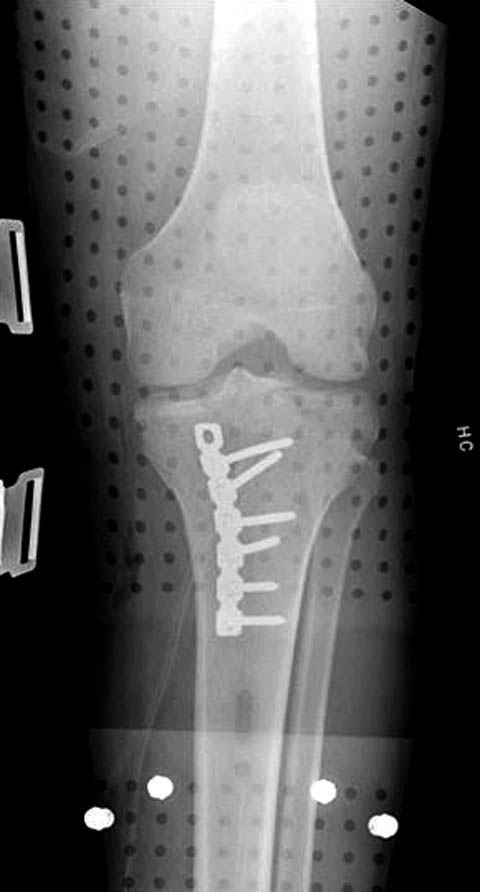

Трудно поверить, что разрекламированная Ортопедическая школа Восточной Украины позволяет такие странные снимки? На прямом снимке сохранен общий контур плато, но не известна судьба импрессии суставной поверхности. На полубоковой?, оставлен без репозиции задне-медиальный отдел, и навряд ли после такой фиксации можно удовлетвориться результатом.

Такая ситуация характерна для многих, когда принимается ошибочное решение, т.е пытаются фиксировать одним имплантом переломы двух мыщелков. Латеральная пластина приемлема только для тех случаев, когда сохраняется интактным медиальный диафизарный кортекс и отсутствует фрагментация на верхушке медиального перелома.

Здесь как раз тот случай, когда результат зависит не только от мастерства хирурга, но и от наличия современных методов исследования. Например, КТ которая поможет рассчитать направления шурупов и установку импланта. Кроме этого, поможет определиться с доступом.

На представленных предоперационных срезах КТ огромный задне-медиальный фрагмент расположен больше кзади, чем медиально. Для планирования, кроме поперечных срезов, надо ориентироваться на корональные срезы, которые укажут топографию верхушки медиального фрагмента.

Представленные снимки не информативны, нужны отдельные качественные снимки коленного сустава и голени без ротации.